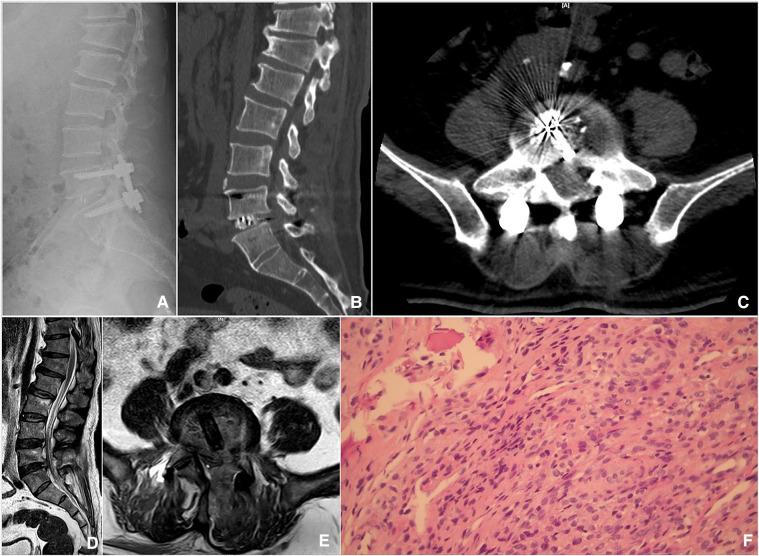

This study aims to investigate the effectiveness and feasibility of biportal endoscopic decompression, debridement, and interbody fusion, combined with percutaneous screw fixation for lumbar brucellosis spondylitis (LBS).

The data of 13 patients with LBS were retrospectively analyzed, who underwent biportal endoscopic decompression, debridement, and interbody fusion, combined with percutaneous screw fixation from May 2020 to June 2022. The patients' clinical data, the duration of operation, the estimated blood loss (including postoperative drainage), and complications were recorded. Clinical outcomes include serum agglutination test (SAT) measures Brucella antibody titer, erythrocyte sedimentation rate (ESR), C-reactive protein (CRP), the visual analog scale (VAS) scores of low back and leg, Japanese Orthopaedic Association (JOA) score, Oswestry Disability Index (ODI), American Spinal Injury Association neurological classification, and lordotic angle were analyzed. All patients were assessed using the modified Macnab criteria at the final follow-up. The intervertebral bone graft fusion was assessed using the Bridwell grading criteria.

The mean operation duration was 177.31 ± 19.54 min, and the estimated blood loss was 176.15 ± 43.79 ml (including postoperative drainage was 41.15 ± 10.44 ml). The mean follow-up period was 13.92 ± 1.5 months. SAT showed that the antibody titers of 13 patients were normal 3 months after the operation and at the final follow-up. ESR and CRP levels returned to normal by the end of the 3-month follow-up. VAS scores of low back and leg, JOA score, and ODI significantly improved after the operation throughout the follow-up period ( < 0.05). Based on the modified Macnab criteria, 92.3% showed excellent to good outcomes. One patient had only a percutaneous screw internal fixation on the decompression side due to severe osteoporosis. One case suffered a superficial incision infection postoperatively that healed with dressing change and effective antibiotic treatment. Bony fusion was obtained in all patients at the last follow-up, including 12 cases with grade I and 1 case with grade II, with a fusion rate of 92.31%.

Biportal endoscopic decompression, debridement, and interbody fusion, combined with percutaneous screw fixation is an effective, safe, and viable surgical procedure for the treatment of LBS.